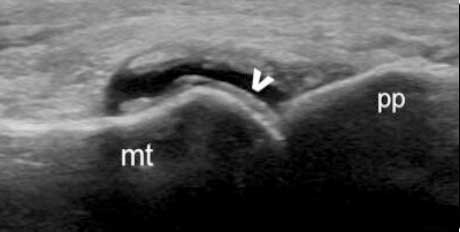

“双轨征”

跖趾关节软骨表面可见高回声不规则增强的软骨滑膜边缘线,呈“双轨征”。

高回声带

软骨表面回声增强,与深面的骨性关节面强回声线形成“双轨征”。